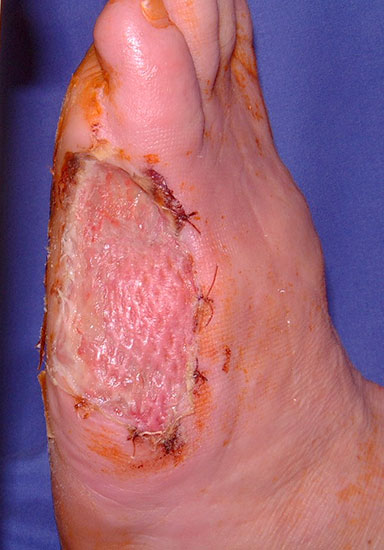

Cave:

Die Knochenenden müssen so gestaltet werden, dass sie keinen Druck auf die Haut aus­üben können. Wenn sich die Wundränder nicht durch Nähte verschließen lassen (z.B. nach Infektion), wird in den nicht belasteten Regionen eine Spalthautdeckung vorgenommen (Abb. 28, 29), wenn eine infektfreie Granulation vorliegt.